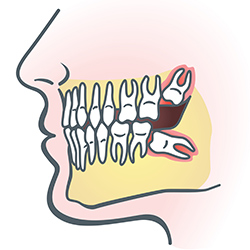

Wisdom Teeth

Wisdom teeth are molars found in the very back of your mouth. These teeth usually appear in late teens or early twenties but may become impacted (fail to erupt) due to lack of room in the jaw or angle of entry. When a wisdom tooth is impacted, it may need to be removed. If it is not removed, you may develop gum tenderness, swelling, or even severe pain. Impacted wisdom teeth that are partially or fully erupted tend to be quite difficult to clean and are susceptible to tooth decay, recurring infections, and even gum disease.

Wisdom teeth are typically removed in the late teens or early twenties because there is a greater chance that the teeth's roots have not fully formed and the bone surrounding the teeth is less dense. These two factors can make extraction easier, as well as making the recovery time much shorter.

In order to remove a wisdom tooth, your dentist first needs to numb the area around the tooth with a local anesthetic. Because the impacted tooth may still be under the gums and imbedded in your jaw bone, your dentist will need to remove a portion of the covering bone to extract the tooth. In order to minimize the amount of bone that is removed with the tooth, your dentist will often "section" your wisdom tooth so that each piece can be removed through a small opening in the bone. Once your wisdom teeth have been extracted, the healing process begins. Healing time varies depending on the degree of difficulty related to the extraction. Your dentist will share with you what to expect and provide instructions for a comfortable, efficient healing process.